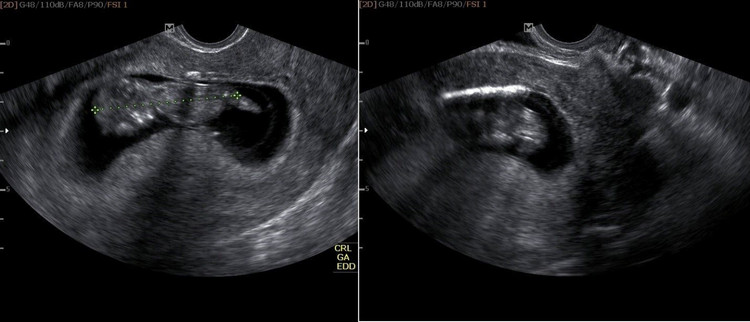

Các bác sĩ phát hiện chị đang có thai tương đương 12 tuần. Hình ảnh siêu âm cho thấy, nằm sát buồng ối là hình ảnh vòng tránh thai, ngay đoạn eo tử cung, nguy cơ gây sẩy thai rất cao.

Hình ảnh vòng tránh thai nằm sát buồng ối của thai nhi

Do nguyện vọng của thai phụ và gia đình, các bác sĩ đã lấy vòng tránh thai ra mà không gây tổn hại tới thai nhi. Sau đó một ngày, chị L. được siêu âm tại Trung tâm chẩn đoán trước sinh và sơ sinh.